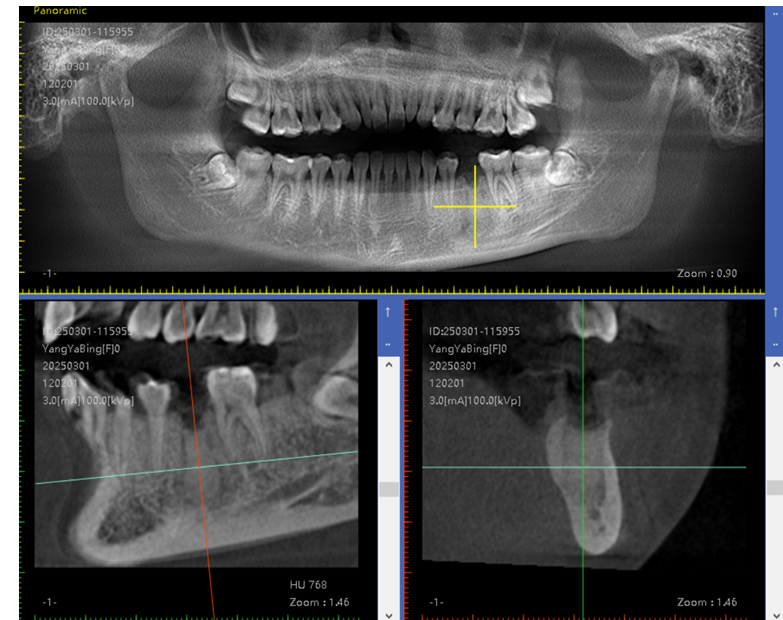

数字化导板技术:通过口腔 CT 扫描获取患者口腔颌骨的精确三维数据,利用计算机辅助设计(CAD)和计算机辅助制造(CAM)技术制作出个性化的手术导板。在牙槽外科手术中,如拔牙、种植牙等,导板可以精确引导手术器械的操作,提高手术的准确性和可预测性,减少手术创伤和并发症,同时缩短手术时间。

自提牙移植技术:是将患者自身的牙齿从一个位置移植到另一个需拔除患牙或缺失牙的位置上,使其在新位置愈合后行使咬合功能,恢复牙列缺损